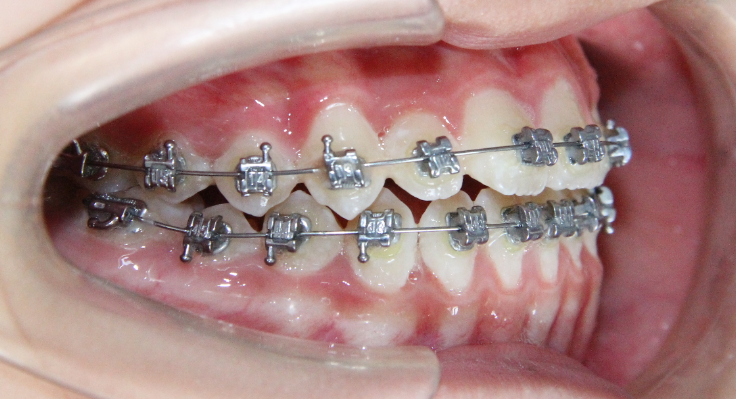

病例1

治疗前

治疗后